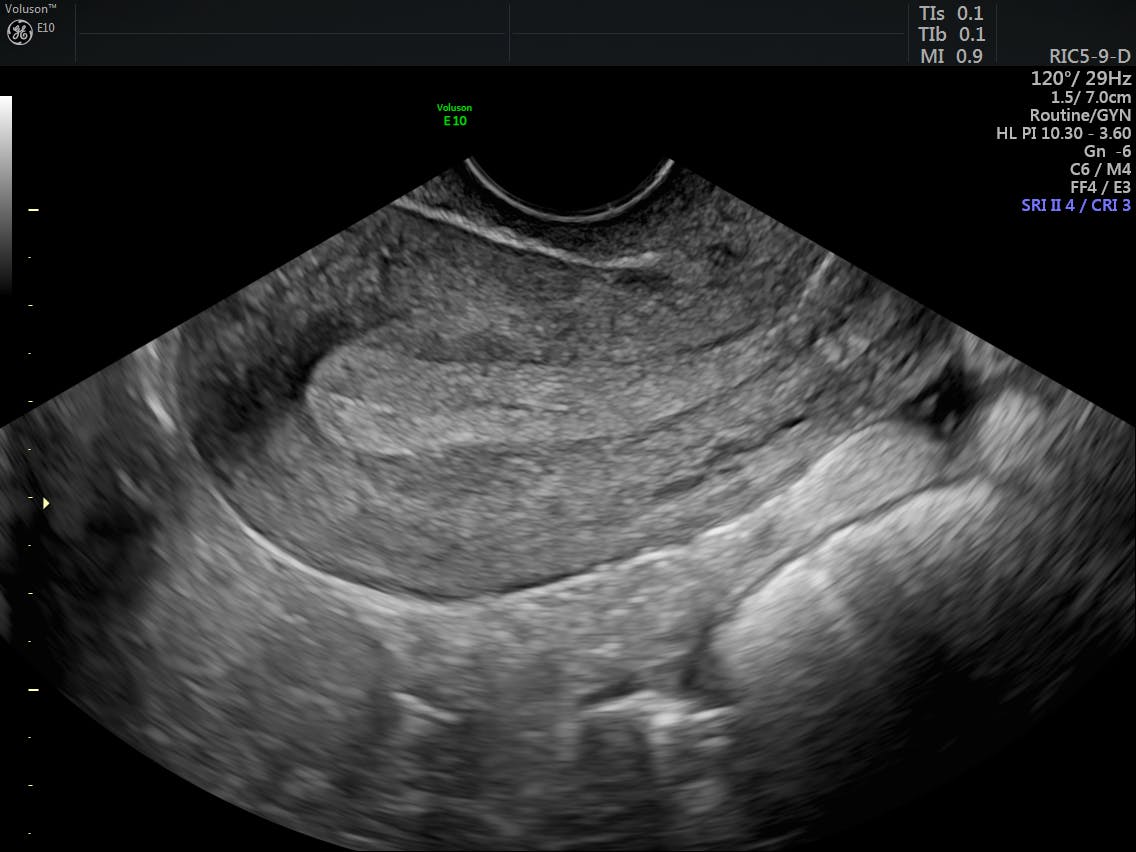

Endometriosis Usg / Signos ecográficos de endometriosis

Transvaginal ultrasound in deep endometriosis: pictorial essay

Transvaginal ultrasound in deep endometriosis: pictorial essay from www.scielo.br